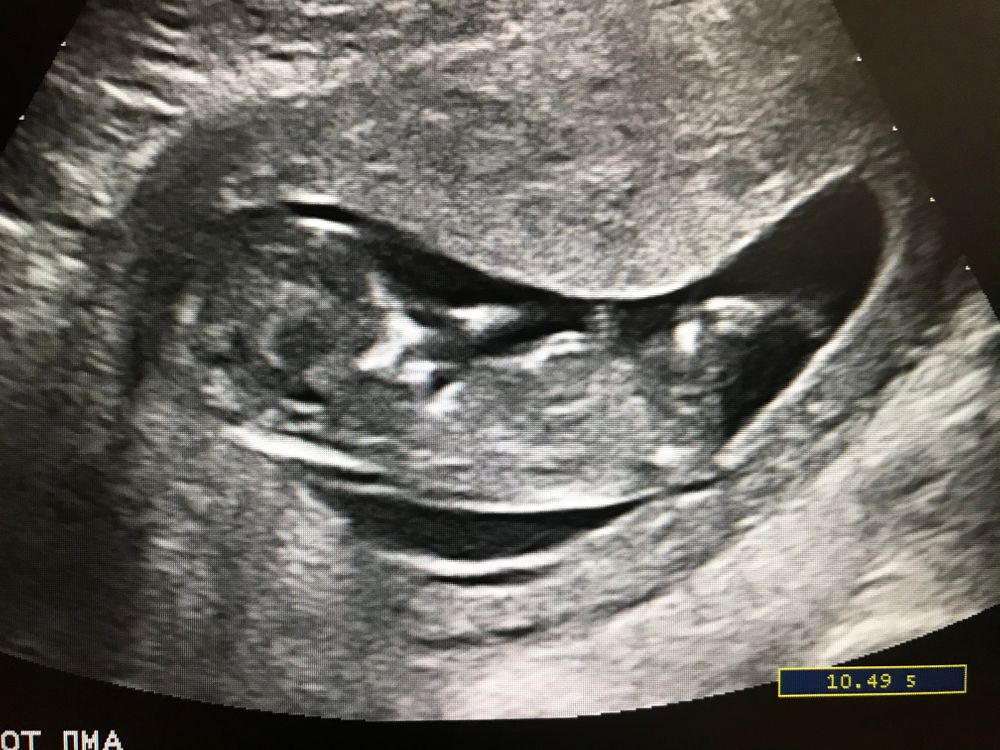

Судя по снимку, справа голова, затем тело, слева ножки. Лежит боком, что между ножек на этом снимке не видно. Обычно на первом скрининге не говорят точно, т.к. половые органы ещё не очень видны, в стадии развития. И сам ребенок, не всегда поворачивается нужным образом. На втором скрининге скажут, я вот тоже жду)

Мне кажется, на этом фото не видно половой бугорок

А где здесь что